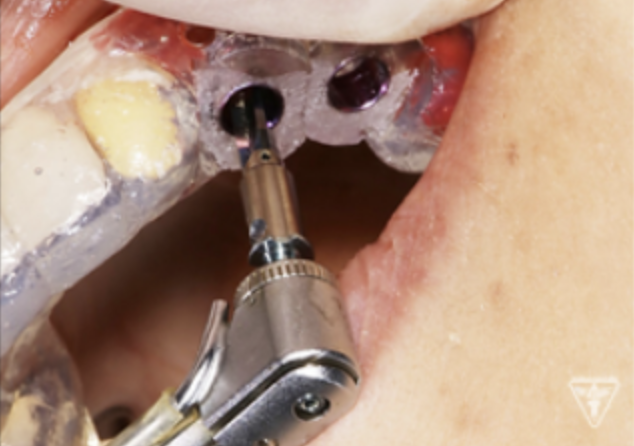

サージカルガイドの作成